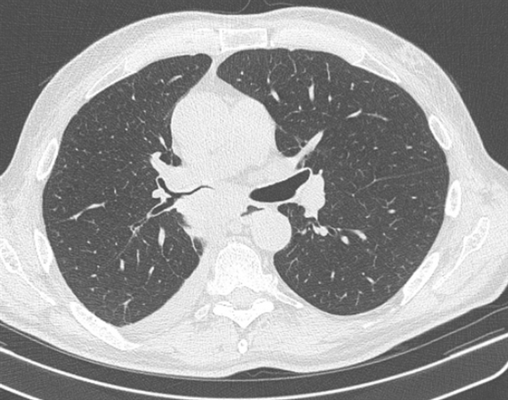

о Метастазы в легких выявляются чаще, чем в костях и печени

Рак легких

Рак легкого – это злокачественная опухоль, источником которой являются клетки бронхиального и альвеолярного эпителия. Это опасное заболевание характеризуется неконтролируемым ростом клеток в тканях лёгкого, склонностью к метастазированию. При отсутствии лечения опухолевый процесс может распространиться за пределы легкого в близлежащие или отдаленные органы. В зависимости от характеристик опухолеобразующих клеток, основными типами рака легких являются мелкоклеточный рак легкого (МРЛ) и немелкоклеточный рак лёгкого (НМРЛ).

Периферический рак постепенно сформировывается в боковых отделах легких, медленно прорастая и ничем себя не обнаруживая. Данная опухоль легкого симптомы долгое время может не давать, они появляются при значительном местном распространении, вовлечении соседних органов и структур, прорастания бронхов. Диагностика рака легких этого типа локализации чаще всего возможна при профилактическом обследовании (рентгенографии или компьютерной томографии).

Фото 2 — Периферический рак (1) верхней доли правого легкого

Онкология легких обычно выявляется при рентгенографическом исследовании грудной клетки и компьютерно-томографическом сканировании (КТ). Диагноз подтверждается биопсией, которая обычно выполняется при трахеобронхоскопии или под КТ контролем.